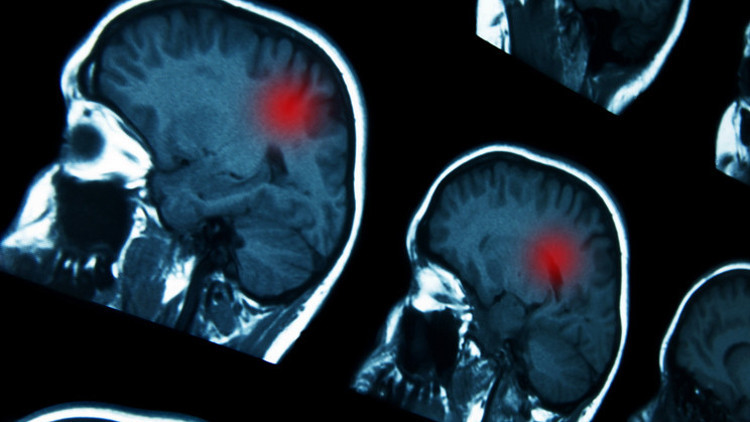

Doktorlar başlangıçta bunun viral bir enfeksiyon olduğunu düşündüler ancak 19 Kasım'da yapılan tomografi (CT) ve MR taramaları, Max'in beyninde büyük bir tümör olduğunu ortaya çıkardı.

Tümörün konumu nedeniyle ameliyat edilmesi mümkün değil. Bu yüzden ailesi, Max'in Almanya'da kanser immün terapisi görebilmesi için bir bağış kampanyası başlattı.

Aile, kanserin türünü netleştirmek için biyopsi sonuçlarını bekliyor; ancak tümör beynin iletişim, konuşma ve hafızadan sorumlu bölgesinde yer alıyor.